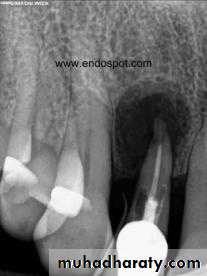

Cyst of long standing may undergo an acute exacerbation which lead to abscess formation.Radiographic Features.

in most cases is identical to periapical granuloma,but, the cyst may be of greater size than the granuloma.Occasionally the apical periodontal cyst exhibits a thin, radiopaque line around the periphery of the radiolucent area, and this indicates a reaction of the bone to the slowly expanding mass.